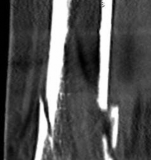

Fig 2.2-3a–h A CT scan with 3D reconstruction.

a–d Sagittal (a–b), coronal (c), and axial (d) images demonstrate displaced posterior, anterolateral, and medial fracture fragments resulting in intraarticular step and gap. The incongruent tibiotalar joint is best appreciated on the sagittal scan.

e–h The 3D reconstructed images show the external fracture anatomy and general alignment.